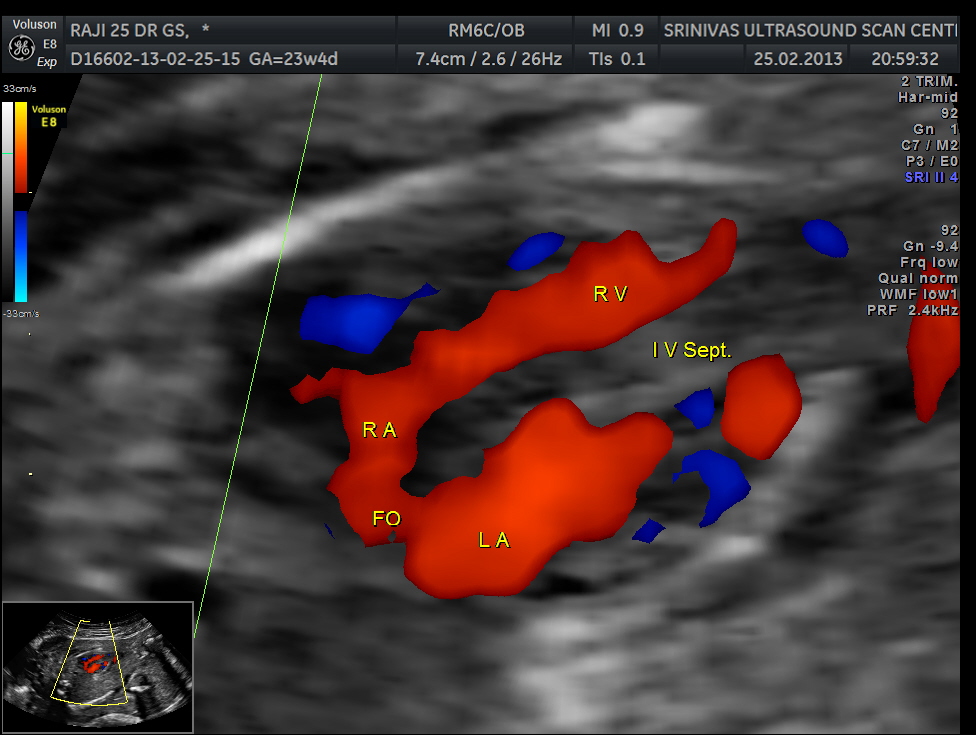

the following colour flow image shows no obvious abnormality.

apart from foramen ovale flow , VSD is seen

Ventricular septal defect seen